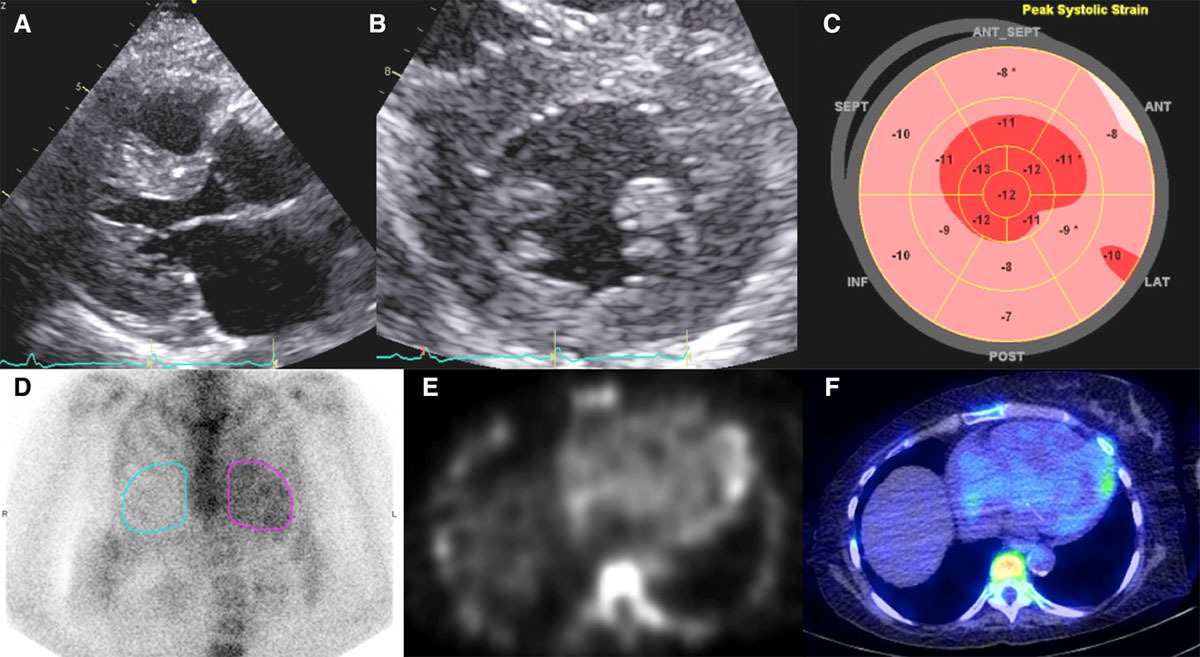

✳️Great case on false positive PYP scan and Target sign on strain echo imaging 'Hydroxychloroquine-Mediated Cardiotoxicity With a False-Positive 99mTechnetium–Labeled Pyrophosphate Scan for Transthyretin-Related Cardiac Amyloidosis' ahajournals.org/doi/10.1161/CI…

✳️Great case on false positive PYP scan and Target sign on strain echo imaging

'Hydroxychloroquine-Mediated Cardiotoxicity With a False-Positive 99mTechnetium–Labeled Pyrophosphate Scan for Transthyretin-Related Cardiac Amyloidosis'